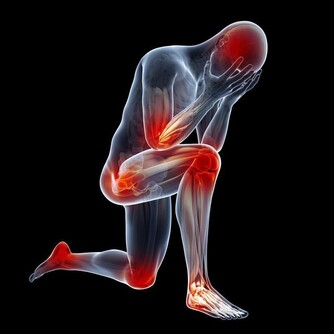

猝死都有那些徵兆呢?來看一下第一個:出現胸悶、呼吸急促的現象

如果在經過大量激烈的運動後,感到胸悶、呼吸急促或者難以呼吸的情況時,這個時候很可能就是你的心臟給你的身體發出的預警。所以出現這種情況,最好即時到醫院檢查一下身體,如果不加以重視的話,多次出現這種情況,很可能會發生猝死。

第二個:出現暈倒

暈倒其實是猝死的最大一種徵兆。其實發生暈厥這種現象,很大程度上都是因為心率減慢或者停止,一旦心率減慢的話,大腦就會產生供血不足,供血不足導致的一個後果就是缺氧,從而就會發生暈倒的現象。所以如果出現暈厥的症狀,要及時檢查,不能放任不管。也許下次就會發生猝死。

第三個:感到疲勞

其實這種疲勞並不是因為腦力或者體力活動而帶來的勞累,是一種毫無徵兆的疲勞。比如說平時並沒有做什麼對身體負擔過重的活動,但就是沒由來地感到勞累,這個時候就要多加註意了,也可能會發生猝死的現象。